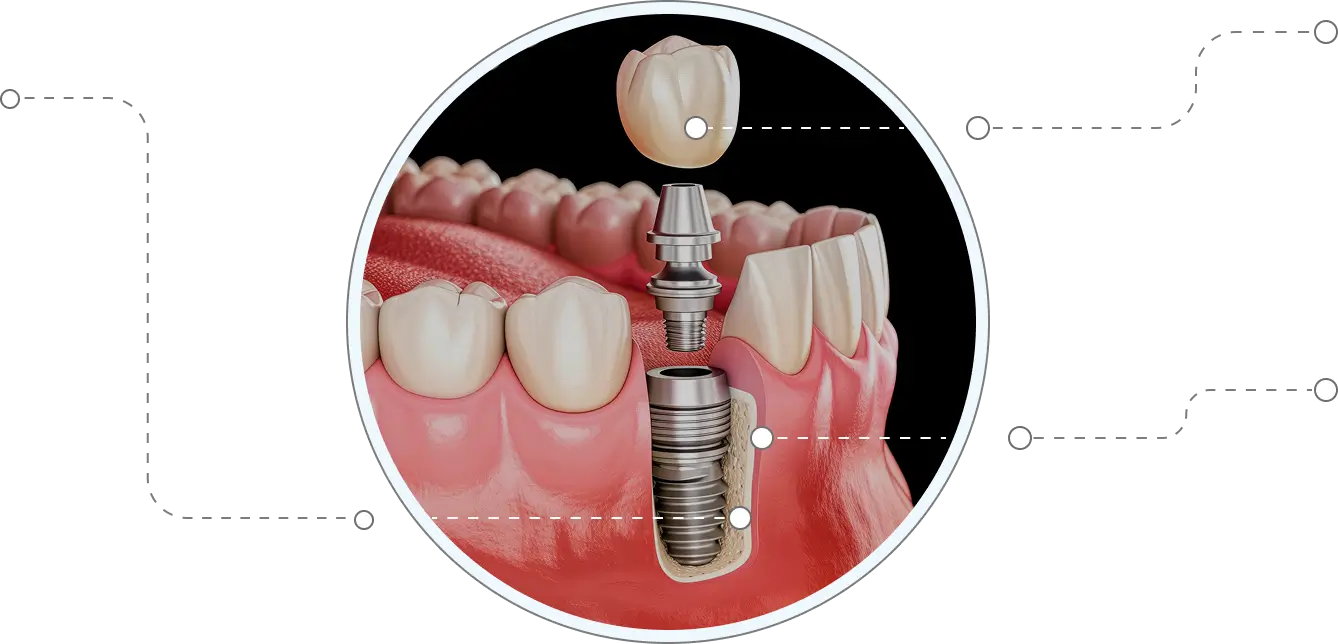

Bone Grafting

To be considered a candidate for dental implants, your jawbone needs to be strong enough to support the implant. The surrounding tissue and nearby teeth have to be in good health. If there is not enough bone to hold it, additional bone can be added through bone grafting.

Crown (Cap)

A crown also called a cap, is attached to the implant to replace the missing tooth.

Implant in Jawbone

First, your dentist will surgically place the implant in your jawbone. Once it fuses to the bone, the implant serves as the new “root.”

1 The Implant

Made of titanium, shaped like a screw or post, is placed into the jawbone.

2 Placing the abutment

Made of titanium, gold, or porcelain, this part attaches to the implant and connects it to the crown.

3 The Crown

Made of PFM, all-metal, or all-porcelain, the crown matches your teeth and is fixed to the abutment.